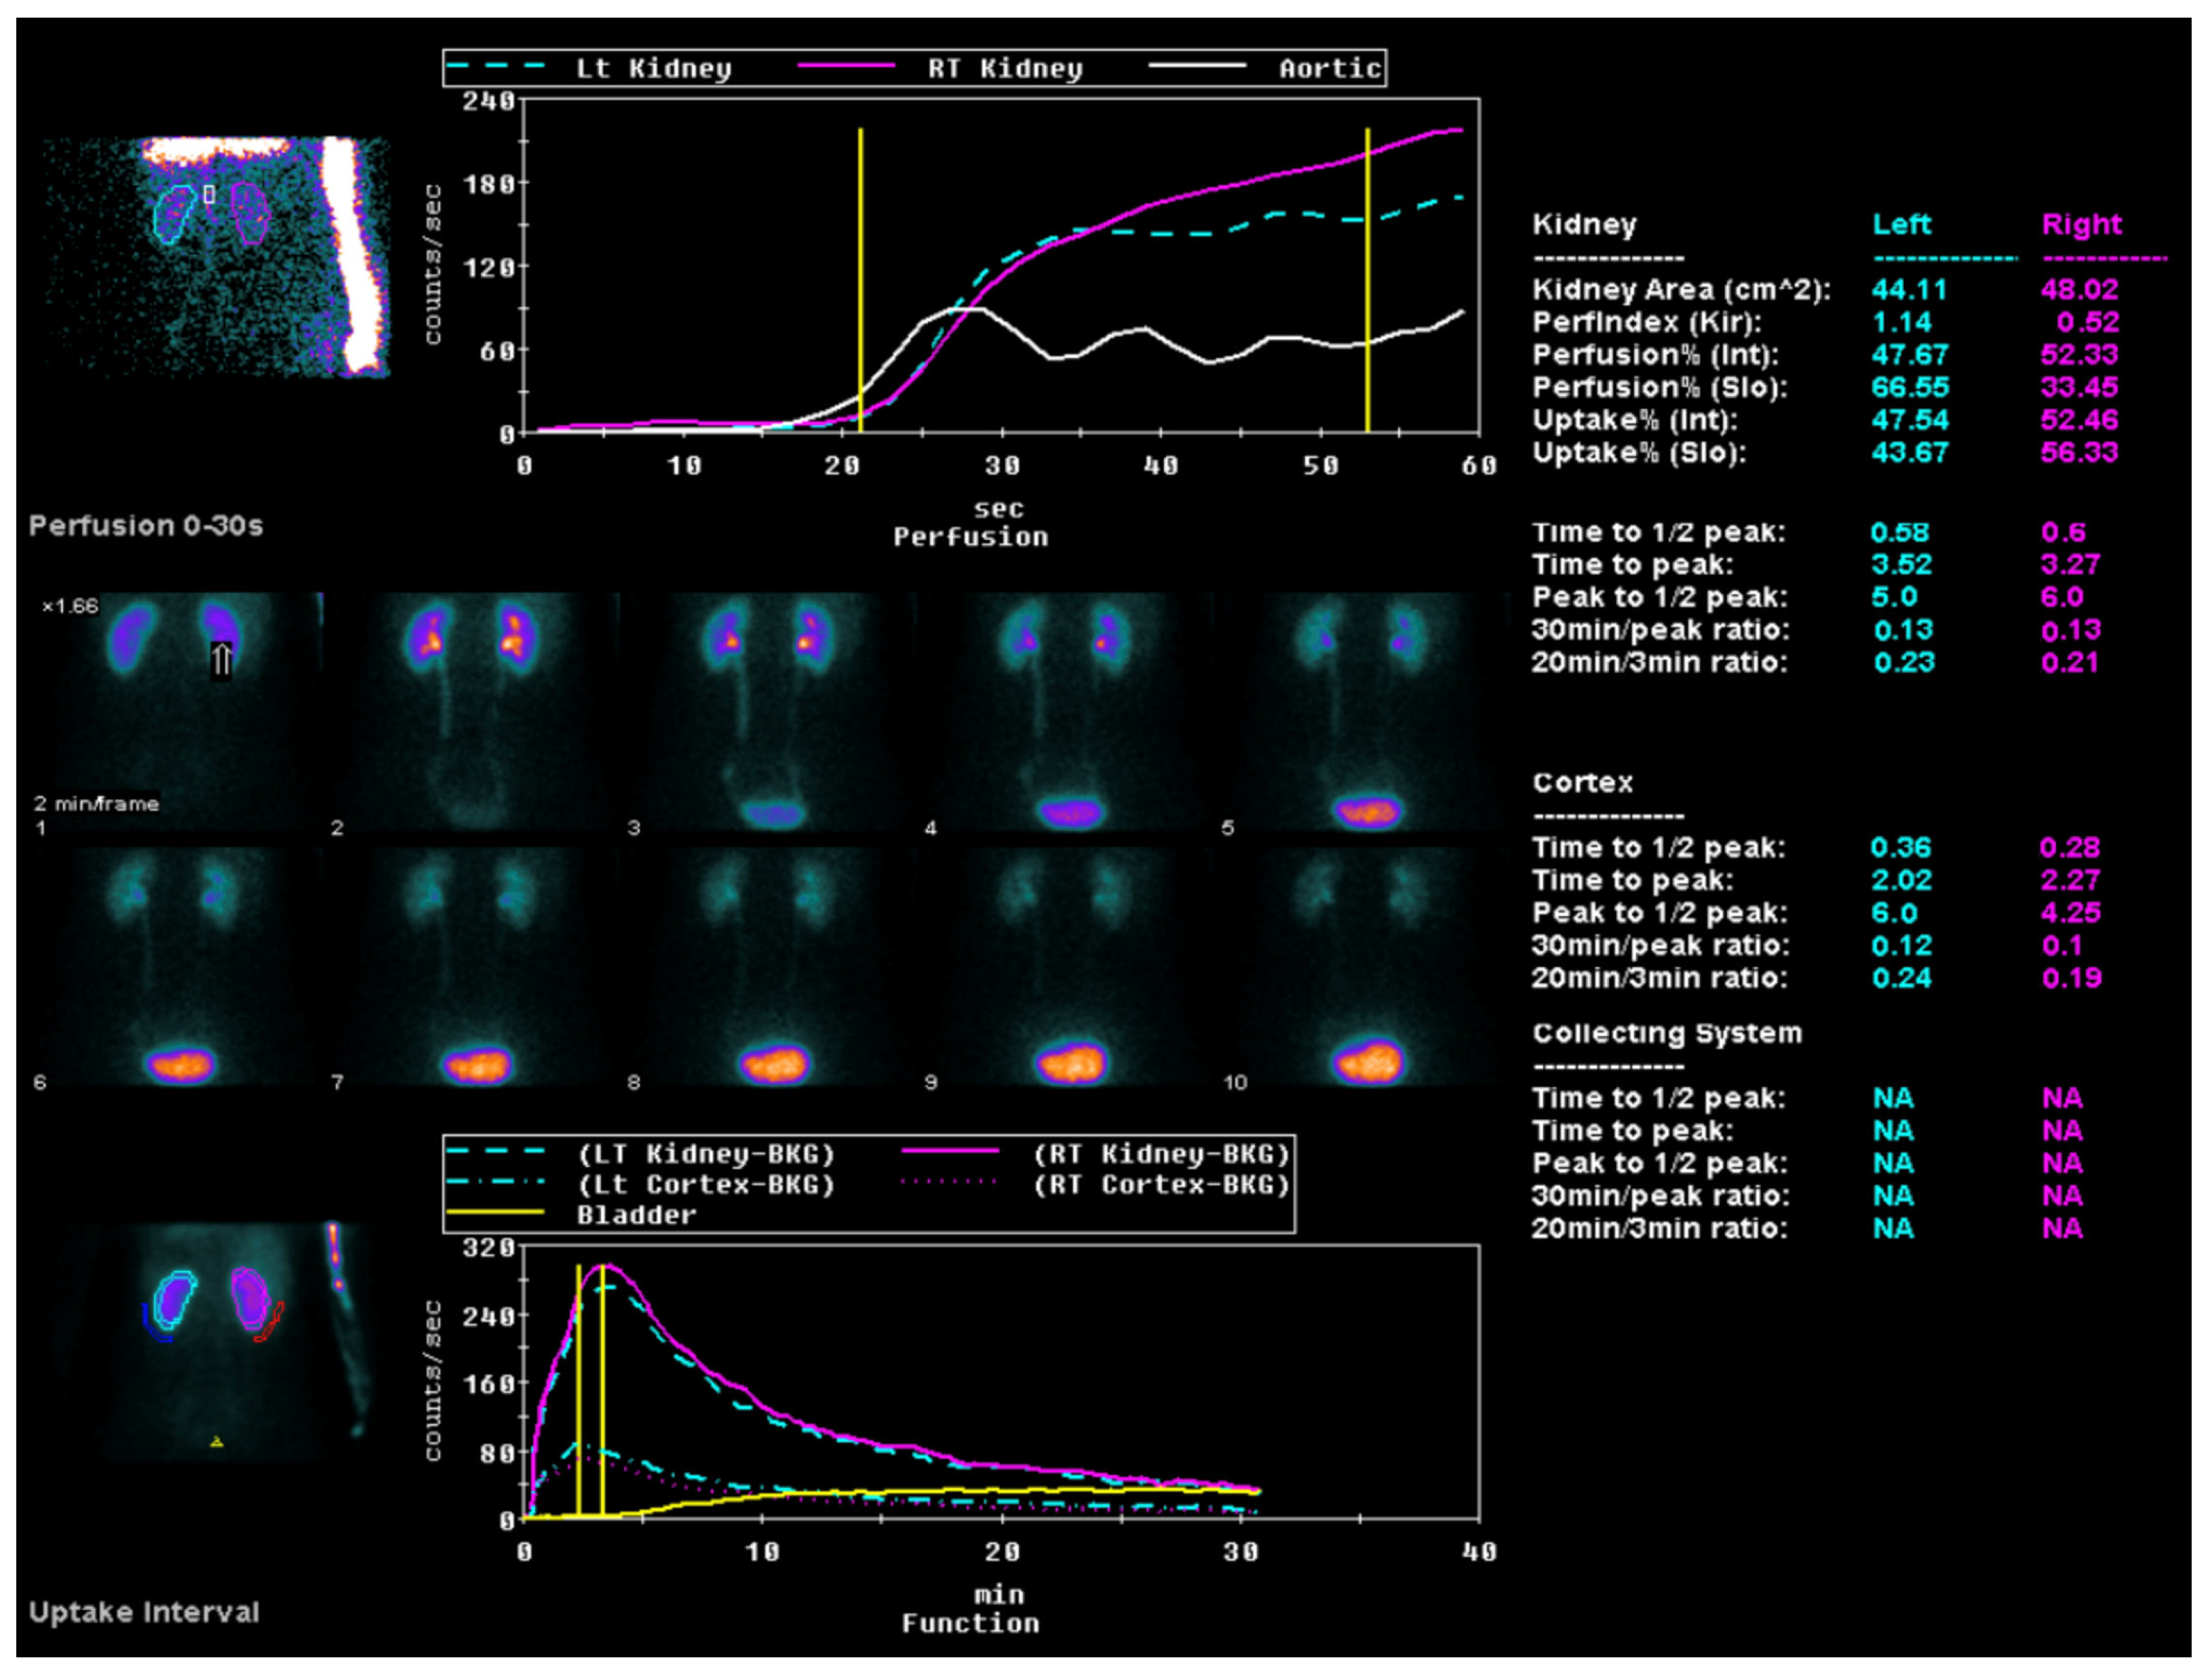

All the study participants underwent ACE inhibitor renography using the radiopharmaceutical 99 mTc-MAG3 (Figure 3) by the consensus report on ACE inhibitor renography guidelines to identify renovascular hypertension [20]. All the patients were instructed to discontinue their ACE inhibitor medication three days before the scan to prevent potential interference with the results. Renal scintigraphy analysis involved the generation of time–activity curves by designating a region of interest (ROI) over each kidney, including the background area, and delineating the aorta. Renal perfusion assessment entailed visual and quantitative analyses of the initial radiopharmaceutical bolus as it passed through the abdominal aorta and into the renal arteries. The relative renal function was evaluated based on the time–activity curve data, focusing on the relative radiopharmaceutical uptake. The Tmax, or time to the peak, was calculated from the radiopharmaceutical injection moment to the peak of the renogram curve. The 30 min/peak ratio, indicative of the renal transit time and parenchymal function, was determined by comparing kidney counts at 30 min post injection to peak counts obtained during the scintigraphy. The T½, or time to the half-peak, was measured from the peak counts to when the renogram curve reduced to half its maximum. Furthermore, the ratio of the whole kidney ROI counts at 20 min to those at 3 min (20 min/3 min ratio) was computed, serving as an essential metric for concurrently evaluating renal clearance and excretion [21]. All the diagnostic evaluations were completed within two months, ensuring a minimum interval of two weeks between each patient’s CT and renal perfusion scans.

The perfusion graph shows the tracer flow through the left and right kidneys and the aorta over time, charted against count rates. A sequential series highlights the tracer distribution in the kidneys during the first 30 s post injection. The uptake graph illustrates longer-term tracer uptake and excretion, focusing on kidney and bladder activity. Quantitative data provide detailed metrics, such as the kidney area, perfusion indices (Tmax, T½, 30 min/peak ratio, and 20 min/3 min ratio) uptake percentages, and peak times, for both kidneys.

Figure 3. ACE inhibitor renography using the radiopharmaceutical 99 mTc-MAG3.